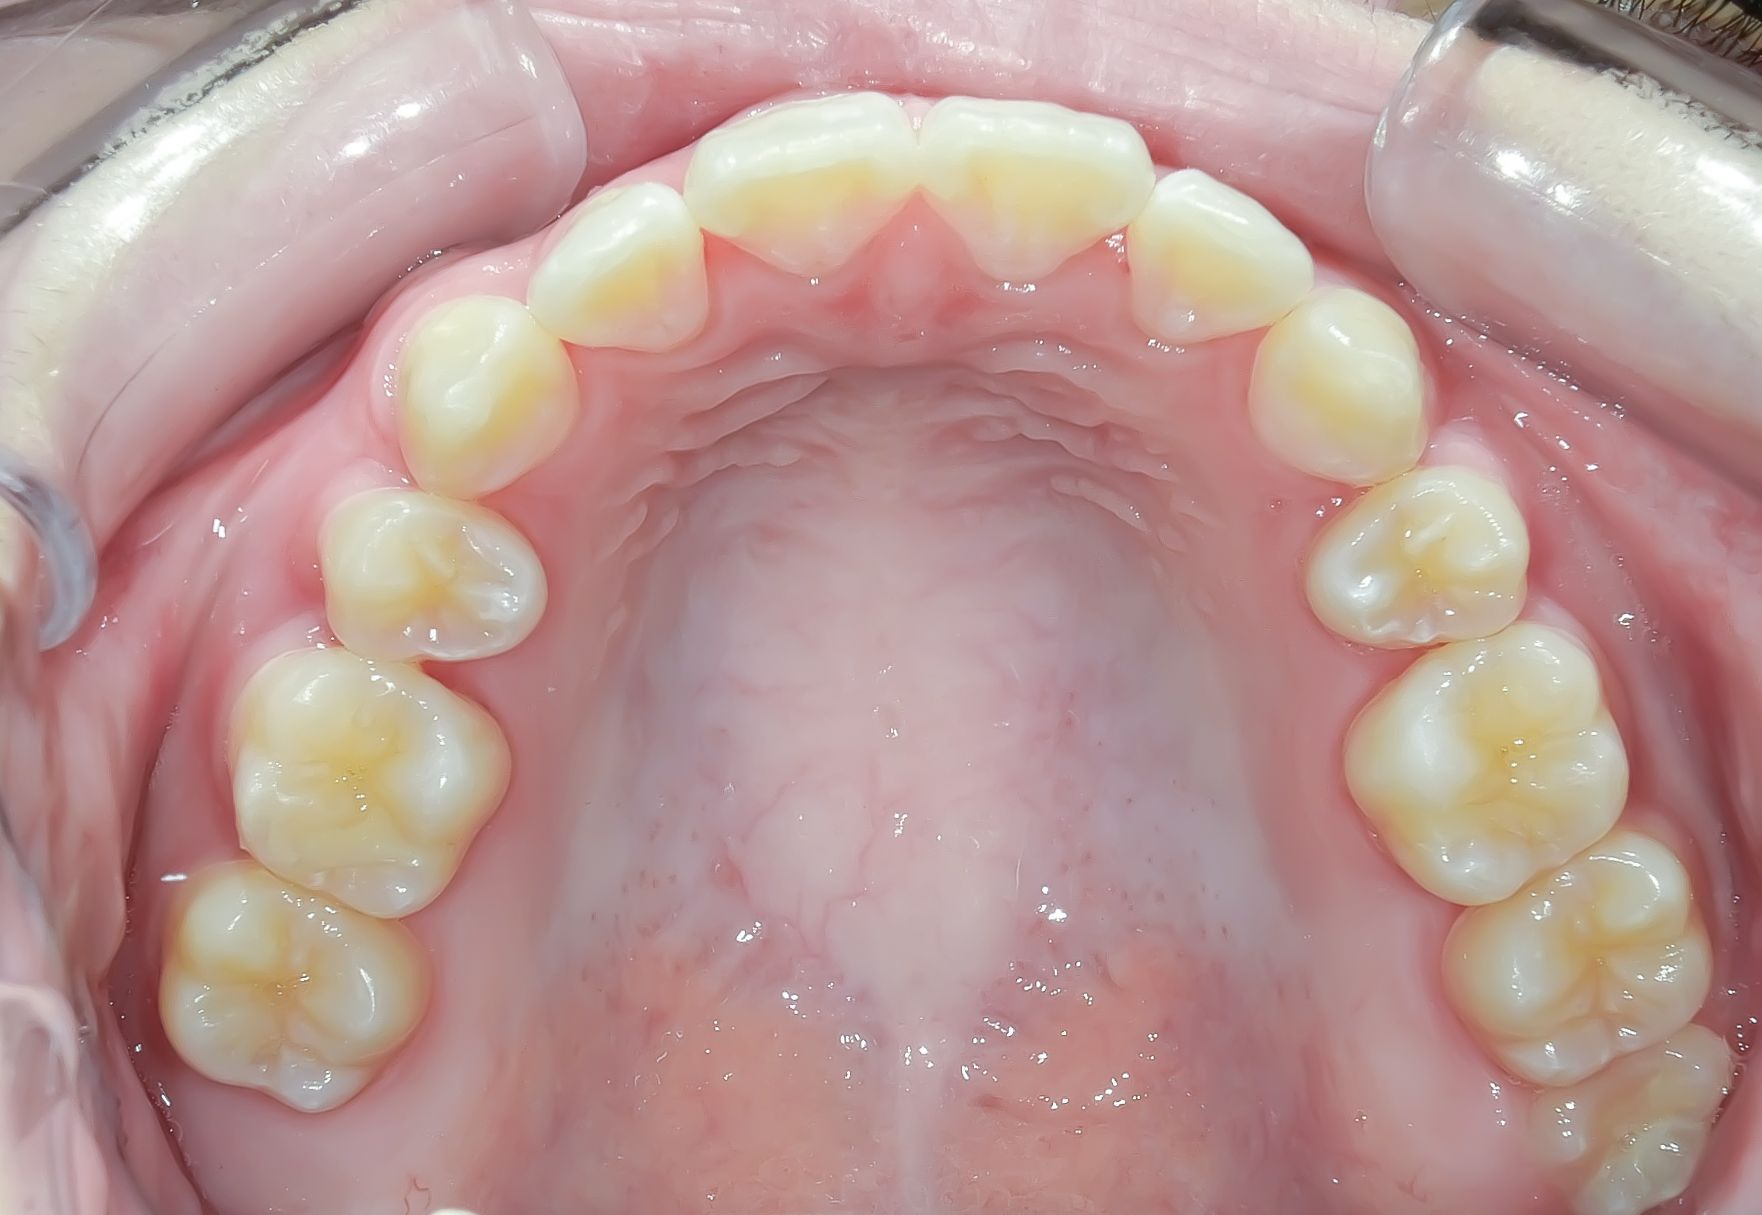

Before

上顎の前歯部あたりに重度のガタガタ(叢生)を認めます。

下顎には軽度の叢生を認めます。